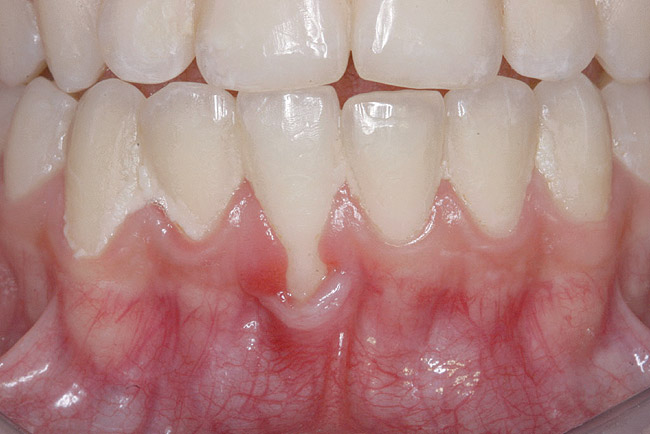

CASE 3 Fig 6. Post-orthodontic Miller Class II recession recommended for orthodontic treatment. Clinical view 5 years after orthodontic treatment showing a buccally displaced root of the lower incisor.

Figure 6

In cases in which adequate lingual bone thickness (≥2.5 mm) is measured on CBCT, orthodontic retreatment should be encouraged (Figure 6 through Figure 8). Most of these patients present with a fixed orthodontic retainer bonded on the lingual aspect of the lower teeth. Therefore, the crown of the affected tooth is splinted and aligned relative to the adjacent teeth, while only the root is displaced toward the labial alveolar plate. Consequently, the orthodontic movement should consist of lingual root torque around a center of rotation placed in the crown. The torque can be easily achieved with rectangular wires or torqueing springs inserted underneath a heavy round base arch, which provides anchorage from the neighboring teeth.